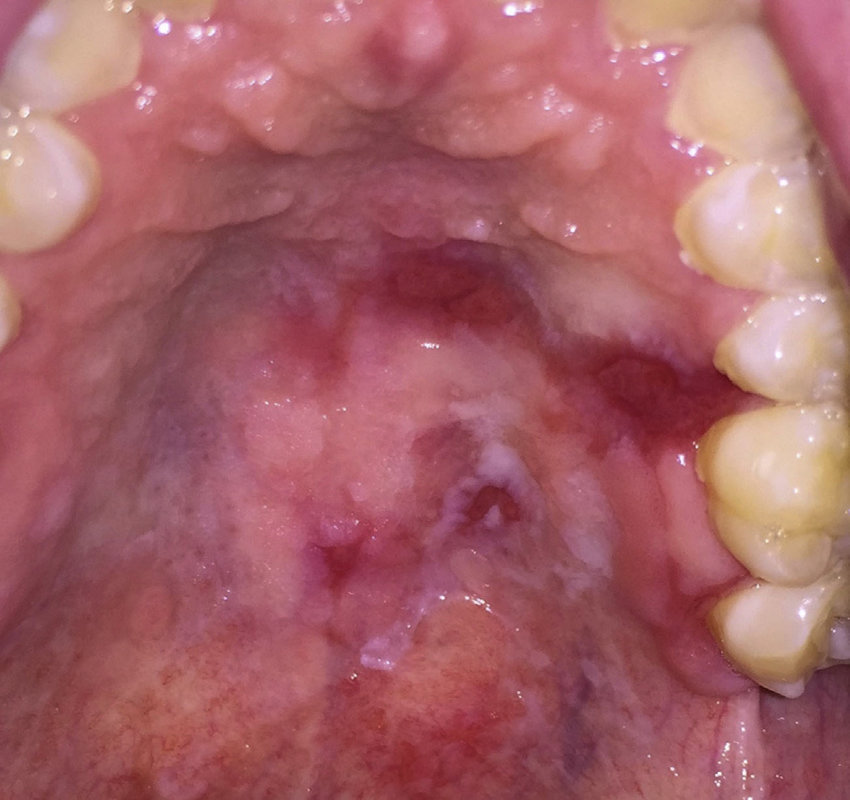

what could cause a blue/purple colour change in the oral mucosa? 4

Purpura – Idiopathic thrombocytopenia purpura and other hematological abnormalities

Haematoma – Bleeding disorders, trauma, drugs

Kaposi’s Sarcoma – HIV infection

Haematological malignancy

Purpura – Idiopathic thrombocytopenia purpura and other hematological abnormalities/clotting conditions - bleeding under the surface of the skin